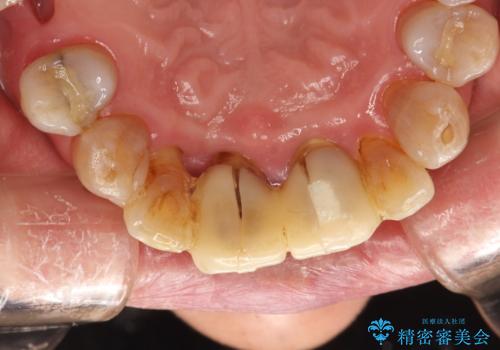

歯周外科前のクリーニング

- 歯周外科を行う前に、しっかりと汚れを除去し外科治療がスムーズに行えるようにとのことでPMTC30分コースを行いました。

治療前のクリーニングを行うことで、より処置がスムーズに行えること・処置後の腫れや感染予防にもなります。また、外科治療をおこなった後は、傷口の治りを待つため、しっかりとブラッシングできない状態になります。そのため処置前に、なるべくお口の中を清潔にしておくことが大切です。